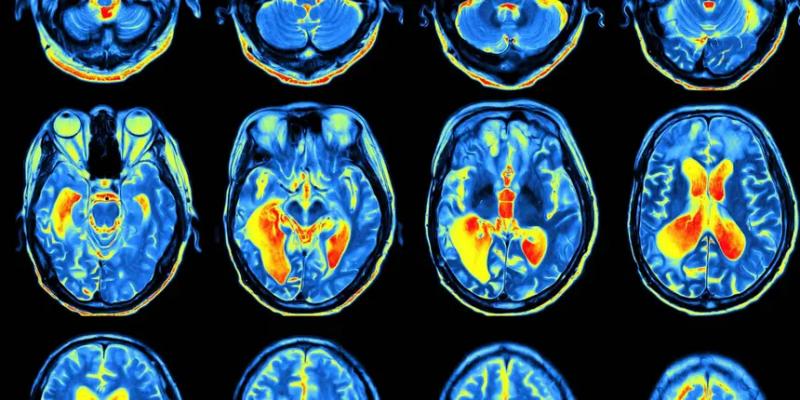

При помощи функциональной магнитно-резонансной томографии (фМРТ) мозга была выявлена более активная область, когда участники сообщали, что видели какой-то рисунок. Эта веретенообразная извилина находится в районе висков. Она активируется как при виде чего-то в реальности, так и при представлении этого. Интересно, что эта активация предсказывает, считаем ли мы что-либо реальным. Далее этот сигнал оценивается передней островковой долей. Активность выше определённого порога воспринимается как реальная, а активность ниже — как воображаемая.